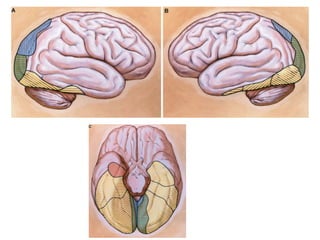

Distribuição cortical

• A ACM irriga toda convexidade cerebral, exceto pólo

occipital, frontal nem a margem superior do hemisférios.

• A região cortical é dividida em 12 áreas de irrigação.

• O tronco principal da ACM pode dividir em três

maneiras: bifurcação (troncos superior e inferior),

trifurcação (dando origem a três troncos, superior,

médio e inferior) ou divisão em múltiplos troncos (quatro

ou mais).

• Em geral uma artéria são responsáveis pela irrigação

de cada uma das áreas corticais,

Distribuição cortical • AACM irriga toda convexidade cerebral, exceto pólo occipital, frontal nem a margem superior do hemisférios. • A região cortical é dividida em 12 áreas de irrigação. • O tronco principal da ACM pode dividir em três maneiras: bifurcação (troncos superior e inferior), trifurcação (dando origem a três troncos, superior, médio e inferior) ou divisão em múltiplos troncos (quatro ou mais). • Em geral uma artéria são responsáveis pela irrigação de cada uma das áreas corticais,